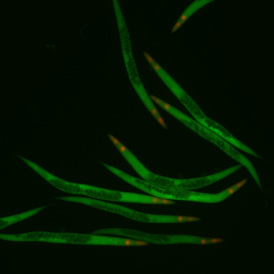

The IF Skeletal Muscle App allows the segmentation of skeletal muscle tissue sections into muscle fibers and connective tissue based on specific IF staining. Outcome parameters are provided, such as the number of muscle fibers and area of the total tissue, muscle fibers, and connective tissue.

Image: Courtesy of Stefania Petrini, Bambino Gesù Children’s Hospital, Rome

The IF Cytoskeleton App detects cytoskeletal structures based on a specific stain. The cell cytoplasm can be detected using other stains. Data can also be exported, including the number of cytoskeletal filaments inside and outside the cell and on the cell membrane, filament length, and total filament area.

The IF Neurite App identifies neuronal cells and cell clusters and their neurites/dendrites. It quantifies the number of neurites/dendrites branching out from a specific neuron, identifies branch points, and exports total neurite/dendrite area, total neurite/dendrite length, average neurite/dendrite thickness, the number of branch points, and the number of endpoints.

The IF Dendrites & Axons App identifies neuronal cells, their dendrites and axon, based on appropriate markers. It quantifies the number of dendrites branching out from a specific neuron. The App provides the total number of dendrites per neuron, including the length of these dendrites and their axons.

Image: Courtesy of Thomas Bastian, Ph.D., University of Minnesota.

The IF Neuronal App identifies neuronal cells and their branches. It quantifies the number of neurites/dendrites branching out from a specific neuronal cell, identifies branching points, and exports total cell area, total branch length, and the number of branch points.

The IF C. Elegans identifies fluorescence stained worms (e.g. c. elegans), categorizes them into different size classes, and detects additional markers within the worms (e.g. dot like markers). Further it analyses the environment arround the worms (e.g. 1000µm distance) spatially for marker intensity. The App outputs area (µm2), length (µm), width (µm), and marker intensity of the detected worms as well as marker intensity in proximity of the worms. Image courtesy: Dr. Simona Ghenea, Institute of Biochemistry, Romanian Academy